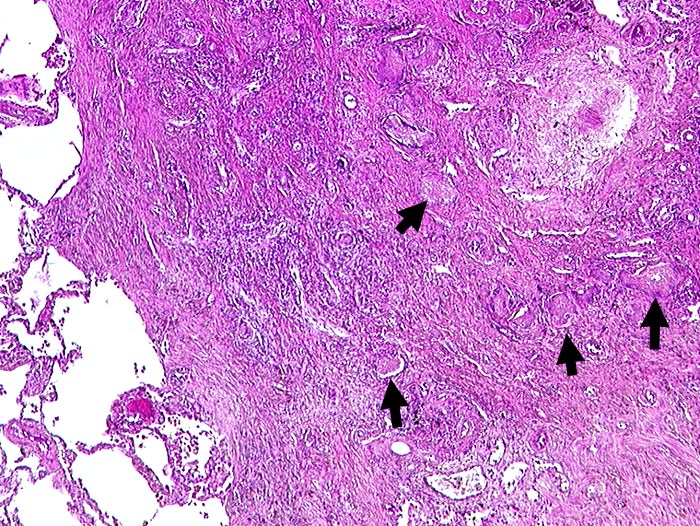

Chronische Pneumocystis jirovecii Pneumonie

Narbengewebe mit schaumigen Einschlüssen.

In den schaumigen Einschlüssen finden sich bei stärkerer Vergrösserung in der Grocottfärbung zahlreiche Erreger.

AIDS. HIV Positivität bekannt seit 2 Jahren bei iv Drogenabusus.